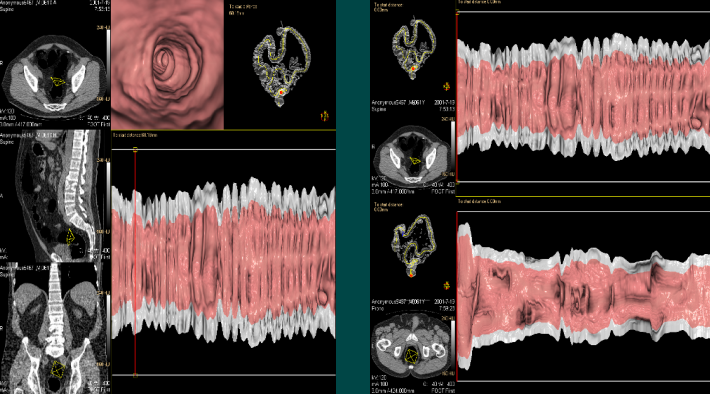

结肠CAD(虚拟切开)

结肠虚拟切开包括“立方体虚拟切开”来显示360 度的三维全景和切开在一个平面上显示的整个结肠二维全景。